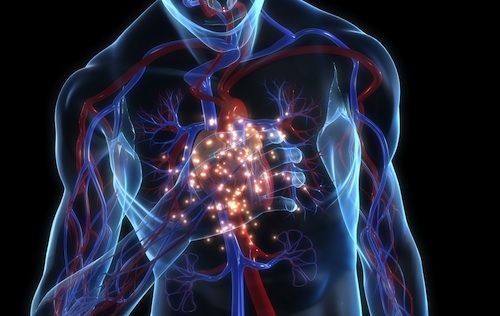

Questa settimana il centro di formazione della Croce Rossa di Caltanissetta ha voluto focalizzare l’attenzione sul fenomeno dell’arresto cardiaco primario, evento che in Europa colpisce circa 70.000 persone e che, se vengono adeguatamente diffuse e insegnate le manovre di rianimazione cardio polmonare e defibrillazione precoce, potrebbero ridurre il numero di decessi. “In questi casi – ha spiegato il centro di formazione della Croce Rossa di Caltanissetta – il ruolo del primo soccorritore riveste la colonna portante dell’impalcatura che segue la catena dei soccorsi”.

La Morte cardiaca improvvisa (Mci) colpisce ogni anno in Italia più di 1000 giovani con età inferiore ai 35 anni (Del Vecchio, 2008). Si tratta di un fenomeno di una certa rilevanza sociale, quindi, con una particolarità preoccupante: la sua mortale insorgenza in soggetti apparentemente sani, perfino negli atleti.

La definizione stessa indica che la Mci è inaspettata: dopo circa un'ora dalla comparsa dei sintomi prodromici (cardiopalmo, tachicardia, dispnea, astenia, altro), non sempre evidenziabili e/o presenti, si manifesta generalmente l'arresto cardiorespiratorio. La presenza o meno di patologie cardiache preesistenti non è un fattore strettamente necessario per l’insorgenza della Mci, anche se molte malattie del cuore ne aumentano esponenzialmente il rischio.

La definizione e l’intervallo di tempo fra l’insorgenza dei sintomi e l’evento fatale, ovvero l’arresto cardiaco, è molto discussa nel panorama scientifico: ciò che pone difficoltà è il fatto che almeno l’80% degli eventi avviene a domicilio e più del 40% senza la presenza di testimoni. Questo rende impervio definire l’evoluzione dell’evento e la sua causa scatenante; gli ultimi studi tendono a considerare questo intervallo di tempo inferiore o pari a 1 ora , basandosi sull’analisi retrospettiva dei certificati di morte o sulle rianimazioni in emergenza.

Appare chiaro che la Mci riguarda tutte le classi di età e non colpisce necessariamente i soggetti con patologie cardiache sottostanti; è fondamentale quindi la prevenzione di tutti quei fattori di rischio che incidono sulla probabilità che l’evento accada, oltre ad un controllo attento e mirato di coloro, come gli atleti, che rientrino nelle categorie definite a rischio.

Importante e fondamentale è anche la velocità e l’efficacia dell’intervento sul soggetto in Mci, cioè l’attivazione della catena della sopravvivenza. La rianimazione cardio-polmonare (Rcp) gioca quindi un ruolo chiave nella sopravvivenza del soggetto colpito da Mci: molti studi mostrano che raddoppia le possibilità di sopravvivenza post-evento, anche se condotta da un laico; inoltre tanto più velocemente viene effettuata, tanto più saranno alte le possibilità che la vittima sopravviva

Importante e fondamentale è anche la velocità e l’efficacia dell’intervento sul soggetto in Mci, cioè l’attivazione della catena della sopravvivenza. La rianimazione cardio-polmonare (Rcp) gioca quindi un ruolo chiave nella sopravvivenza del soggetto colpito da Mci: molti studi mostrano che raddoppia le possibilità di sopravvivenza post-evento, anche se condotta da un laico; inoltre tanto più velocemente viene effettuata, tanto più saranno alte le possibilità che la vittima sopravviva (Zipes, 2007; Fuster, 2009; Modi, 2011).